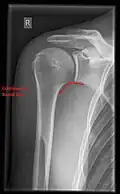

- Y-projection

The lateral contour of the shoulder should be positioned in front of the film in a way that the longitudinal axis of the scapula continues parallel to the path of the rays. This method reveals:[26]

- The horizontal centralization of the humerus head and socket

- The osseous margins of the coraco-acromial arch and hence the supraspinatus outlet canal

- The shape of the acromion

This projection has a low tolerance for errors and, accordingly, needs proper execution.[26] The Y-projection can be traced back to Wijnblath’s 1933 published cavitas-en-face projection.[27]

-

CR. shoulay film. -

Transaxillary conventional radiography -

Y-projection conventional radiography